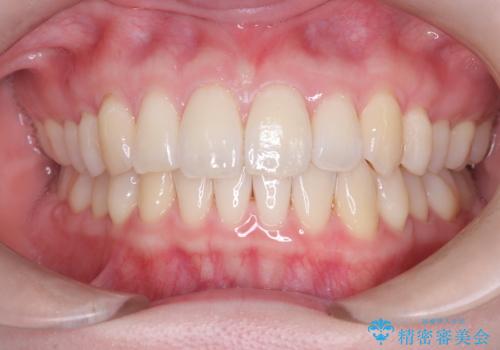

[前歯のねじれ 部分]ワイヤーとマウスピースの併用矯正治療

担当医 大元洋佑

![[前歯のねじれ 部分]ワイヤーとマウスピースの併用矯正治療 の症例 治療前](https://seimitsushinbi.jp/wp/wp-content/uploads/2024/11/IMG_3012-500x350.jpg?v=1731313349)

![[前歯のねじれ 部分]ワイヤーとマウスピースの併用矯正治療 の症例 治療後](https://seimitsushinbi.jp/wp/wp-content/uploads/2024/11/d62ebcf4699c90efb9ffd5ed659b7480-500x350.jpg?v=1731313408)